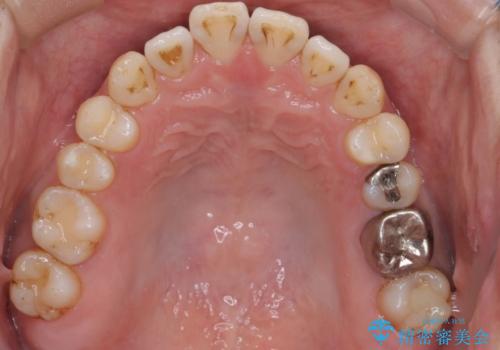

- 前歯の出ているのが気になる、下唇を噛んで痛いとのことで来院された患者様です。マウスピース矯正をご希望でした。

奥歯の噛み合わせはしっかりしていましたので、奥歯の動きは最小限にし、前歯の並びに集中した治療計画+インビザラインのシミュレーションを作成しました。

奥歯の噛み合わせは整っていたため、前歯の並びを美しく修正することに専念できました。マウスピース矯正による治療で短期間で改善しました。